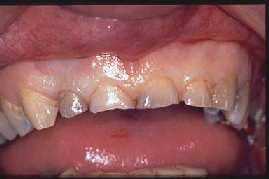

Practicada para "alargar" las piezas dentales" y ganar tamaño clínico en piezas atricionadas o desgastadas.

PRE  OPERATORIO